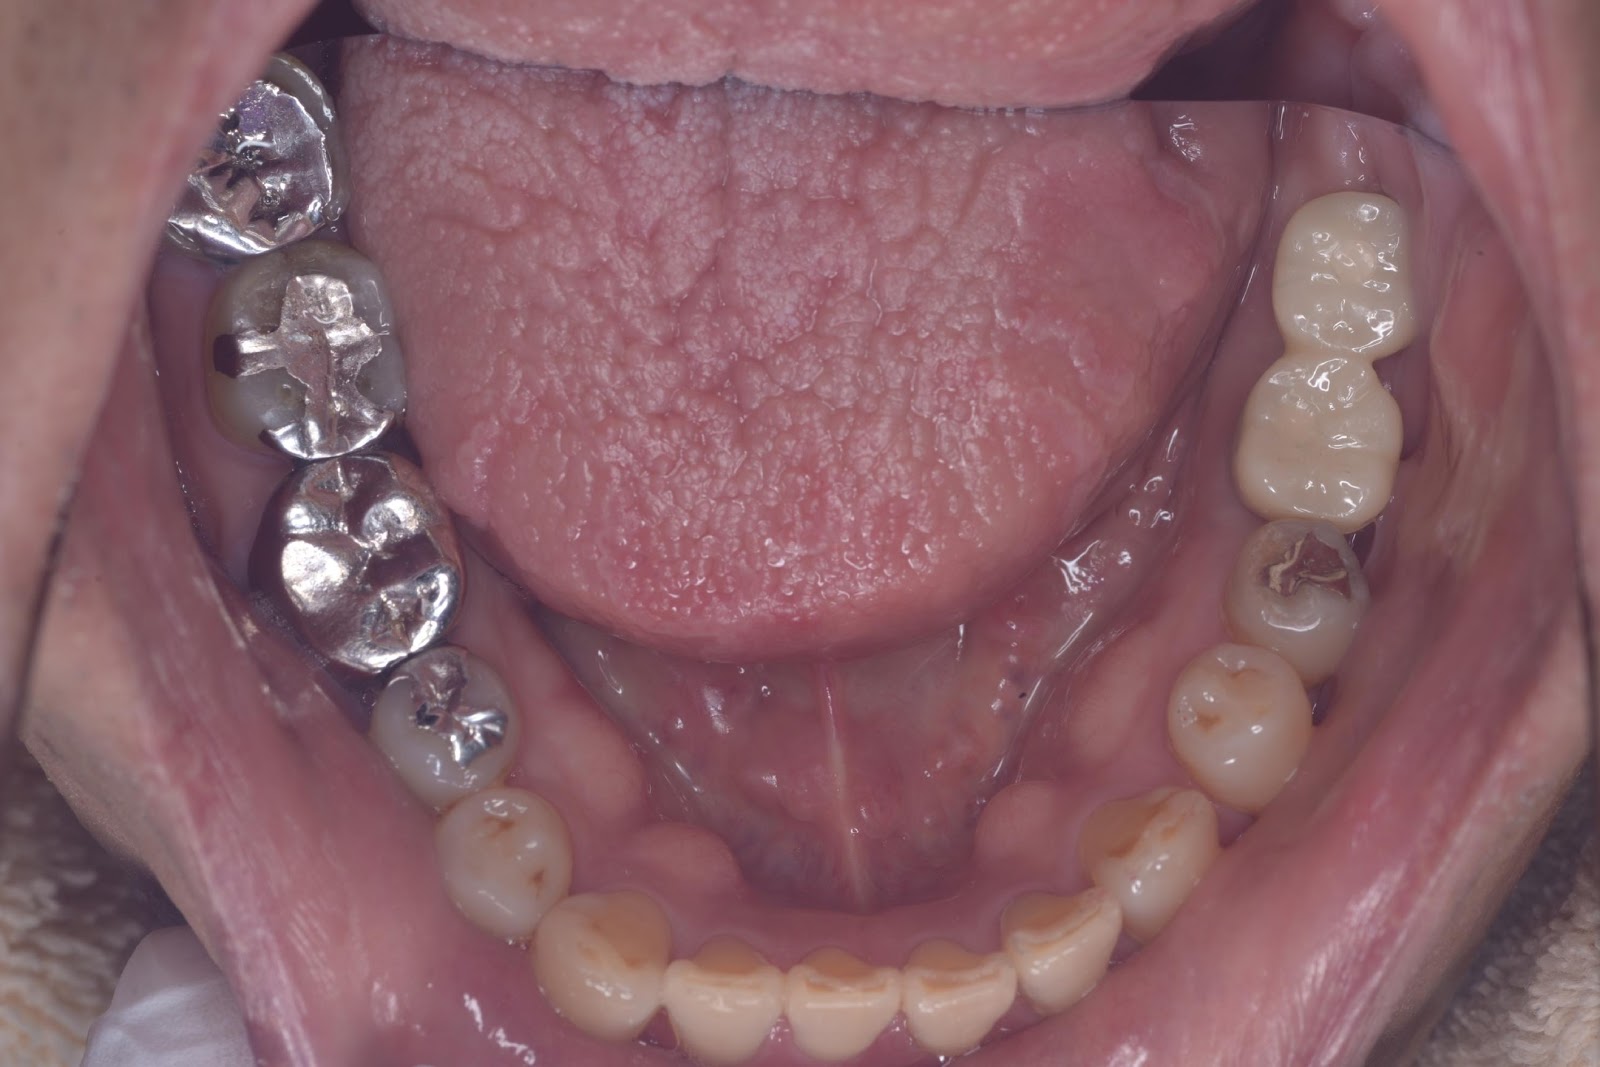

インプラント埋入

50代 女性

40代 女性

20代 男性

60代 男性